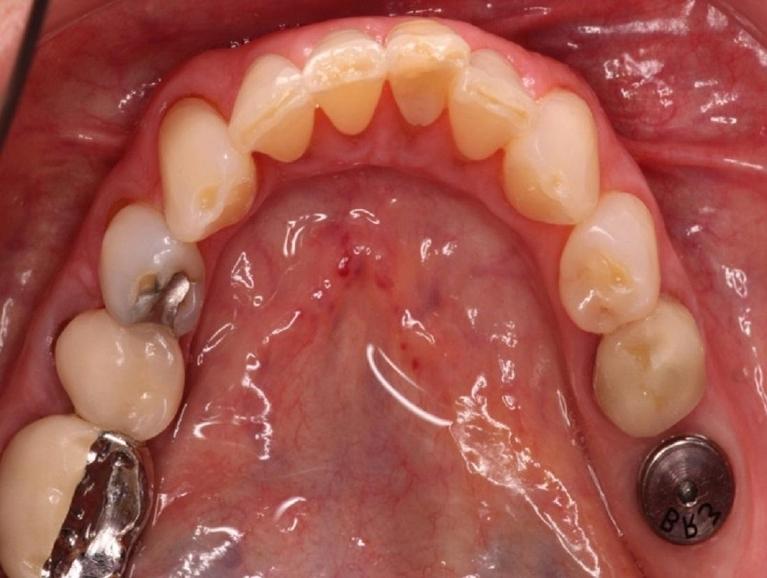

Dr. Uhl places the implant in the jawbone using a small titanium post that replaces the root of your missing tooth. Over time, the implant bonds with surrounding bone and tissue. This forms a secure foundation for the dental crown that Dr. Uhl eventually places over it. Dental implants can be used to replace one or more missing teeth, hold a dental bridge in place, secure a loose denture, or replace dentures with a permanent, fixed solution.

Made of biocompatible titanium, the implant post is placed surgically in your gum and allowed to heal throughout several months. During this time, the implant fuses fully with surrounding bone and tissue. After healing, Dr. Uhl attaches a porcelain crown to it that restores your appearance and allows you to eat, speak, and smile comfortably and with confidence.